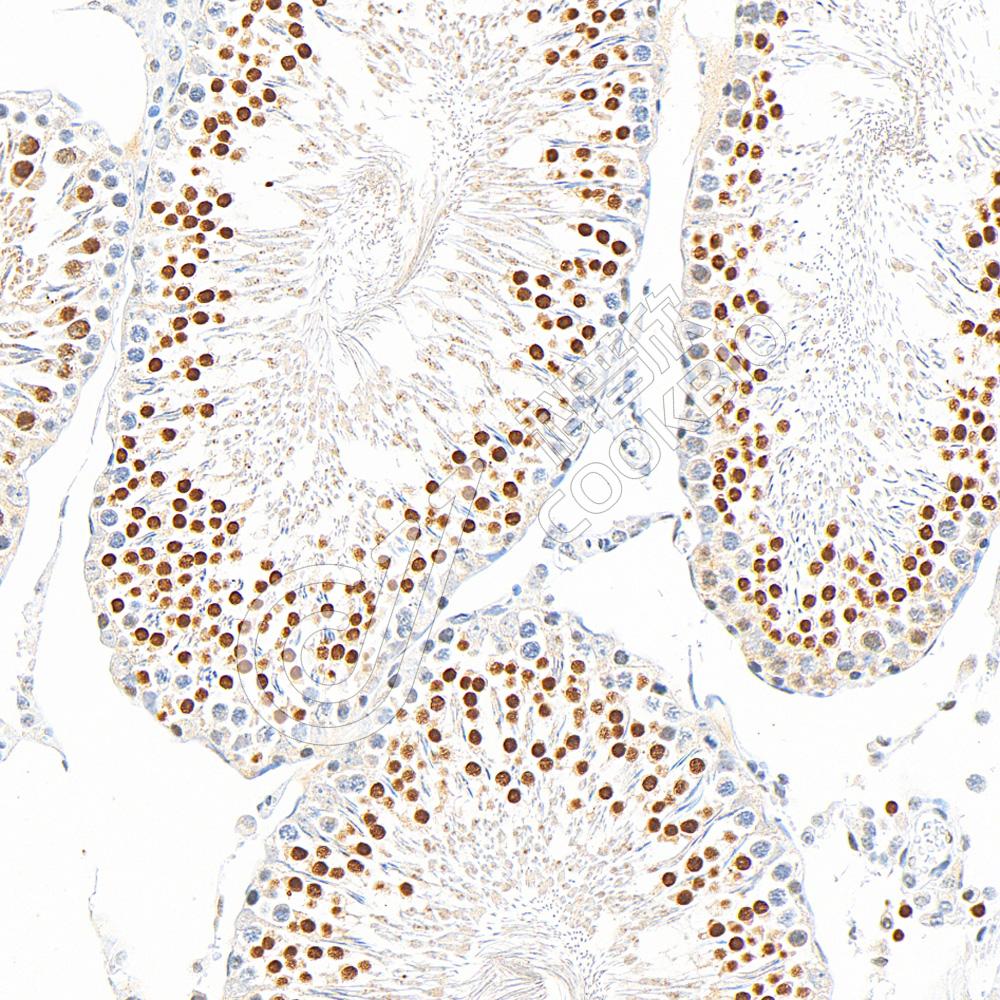

IHC检测GSK3 beta蛋白(货号 K1335082).

样品: 大鼠睾丸, 4%多聚甲醛 (货号KSG1101) 固定12-24小时.

抗原修复: 柠檬酸抗原修复液(干粉, pH 6.0) (KSG1201), 98℃, 20分钟.

—抗: 1: 800稀释, 4℃ 孵育过夜.

二抗: S-vision免疫组化多聚二抗(山羊抗兔),即用型 (货号KB3906), 室温孵育20分钟.